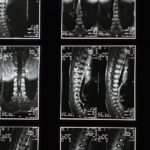

La cruralgie est souvent le résultat d’une compression du nerf crural, conséquent d’une hernie discale ou d’autres problèmes vertébraux. Cette compression entraîne des douleurs qui peuvent irradier de l’arrière du dos jusqu’à la cuisse. Les symptômes incluent des douleurs aiguës, des picotements ou même une sensation de faiblesse dans les jambes. Un diagnostic précis est essentiel pour cheminer vers une guérison adéquate.

Différents facteurs peuvent mener à l’apparition de la cruralgie. Parmi eux, les hernies discales, l’arthrose lombaire, ainsi que des mouvements répétitifs ou des traumatismes des tissus environnants. La prise de conscience de ces causes permet d’éviter certains comportements pouvant aggraver la douleur et de renforcer la prévention.

Avant de mettre en œuvre des stratégies, il est essentiel de comprendre la cruralgie. Elle se manifeste par des douleurs qui irradient de la région lombaire vers l’avant de la cuisse, causées par des facteurs tels que les hernies discales ou le stress musculaire. Les symptômes incluent sensations de brûlure, faiblesse musculaire et picotements. En identifiant ces douleurs, il devient plus facile de choisir les bonnes approches pour les atténuer.